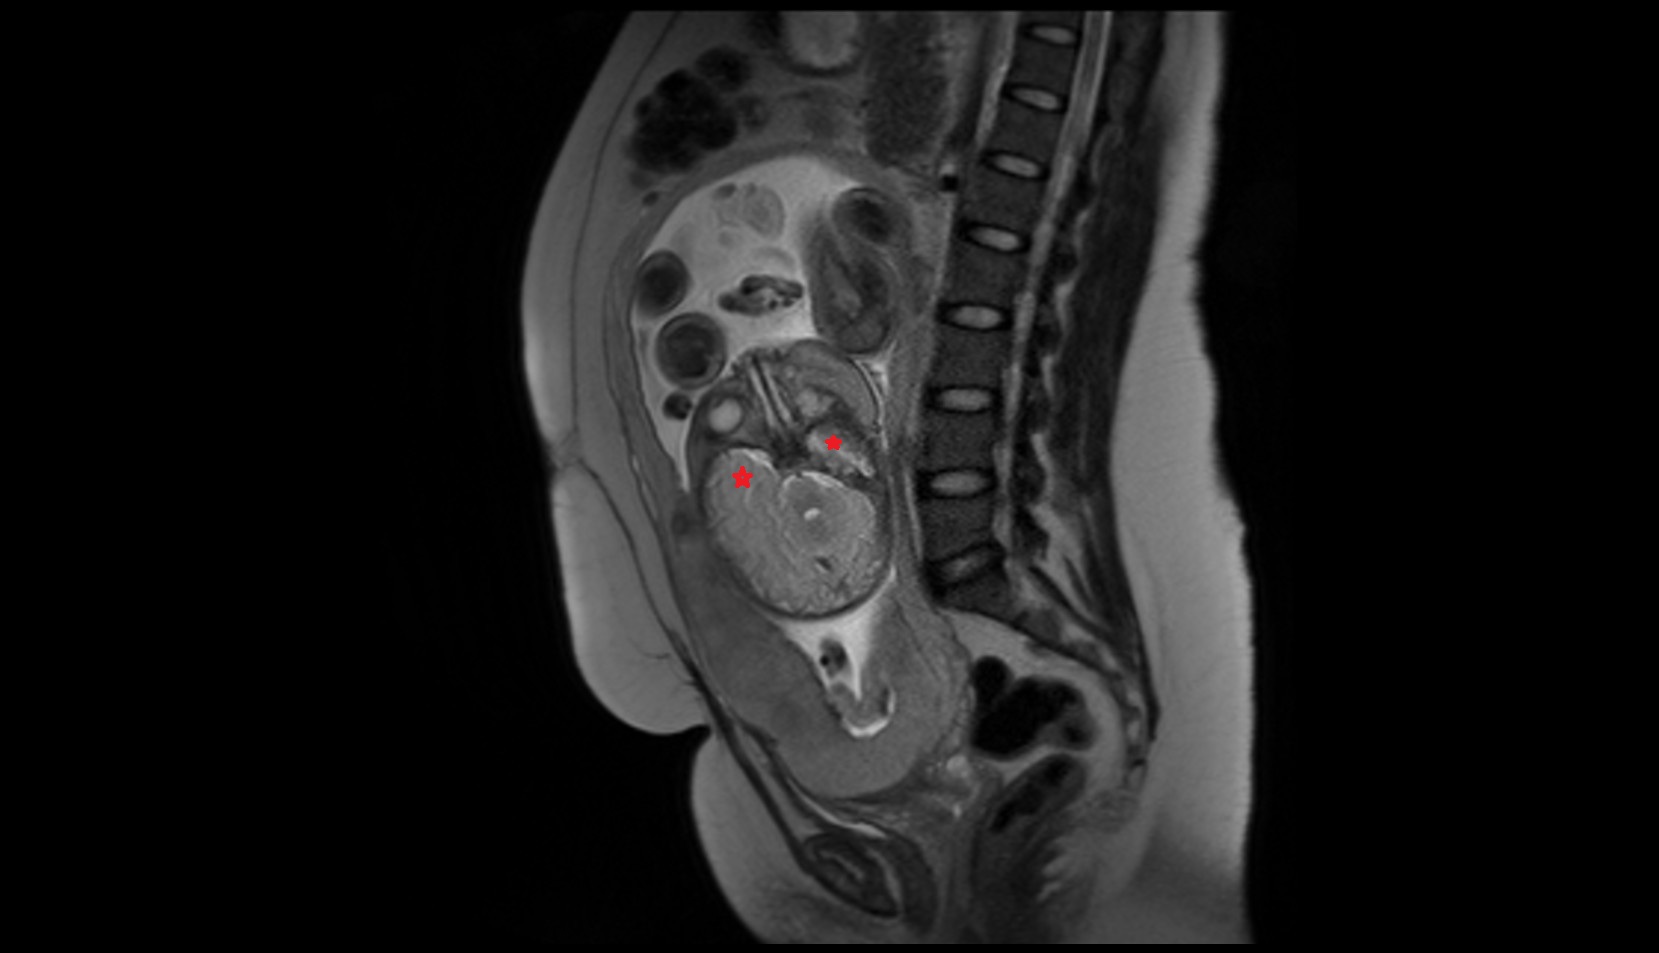

- Placenta

- Uterus (pregnancy)

- Amniotic fluid

- Umbilical cord

- Urinary Bladder in Pregnancy

- Cervix in Pregnancy

- Vagina in Pregnancy

- Fundus of uterus in pregnancy

- Fetal brain

- Maternal ovaries